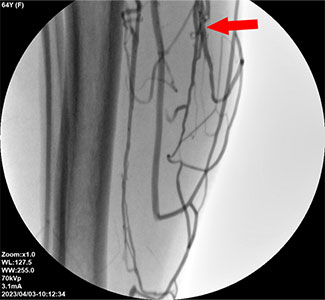

The cause of recurrent varicose veins is the failure to fully seal the affected veins, including the small branch veins.The cause of recurrent varicose veins is clear, thus it is important to identify the reason for the recurrence first. There are two main reasons why varicose veins recur. One is when a previously unaffected vein develops a problem, and the other is when symptoms return in a vein that was treated before. In particular, recurrence in a previously treated vein occurs when the vein was not completely sealed, allowing a new reflux pathway to form. It also includes cases where minor reflux in the small branch veins around the treated vein was overlooked. Ultimately, the main cause of recurrence is the failure to examine and fully seal even the small branch veins.